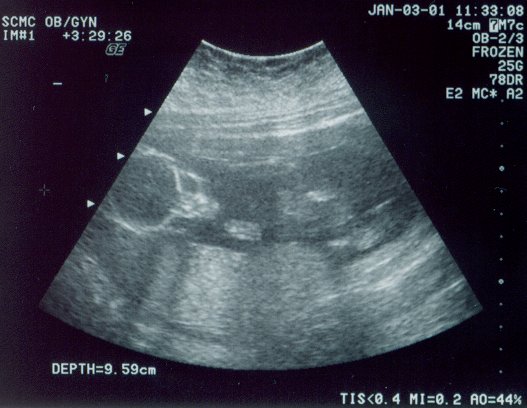

January 3 Had trouble hearing her on the Doppler, and seeing her on the ultrasound, but we finally found out why: Rachel was doing The Twist, The Hokey-Pokey, The Monkey, and The Hustle, all rolled into one. But we finally saw her. #1